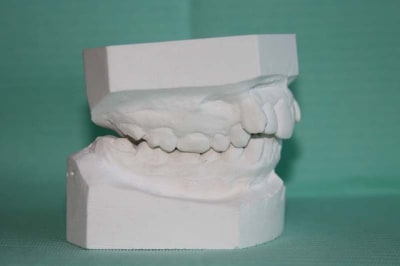

MOULAGES

Moulage 3 kvumyd - Eugenol

Moulage 1 vlrapq - Eugenol

Moulage 2 dllhb9 - Eugenol

Moulage 4 etnevt - Eugenol